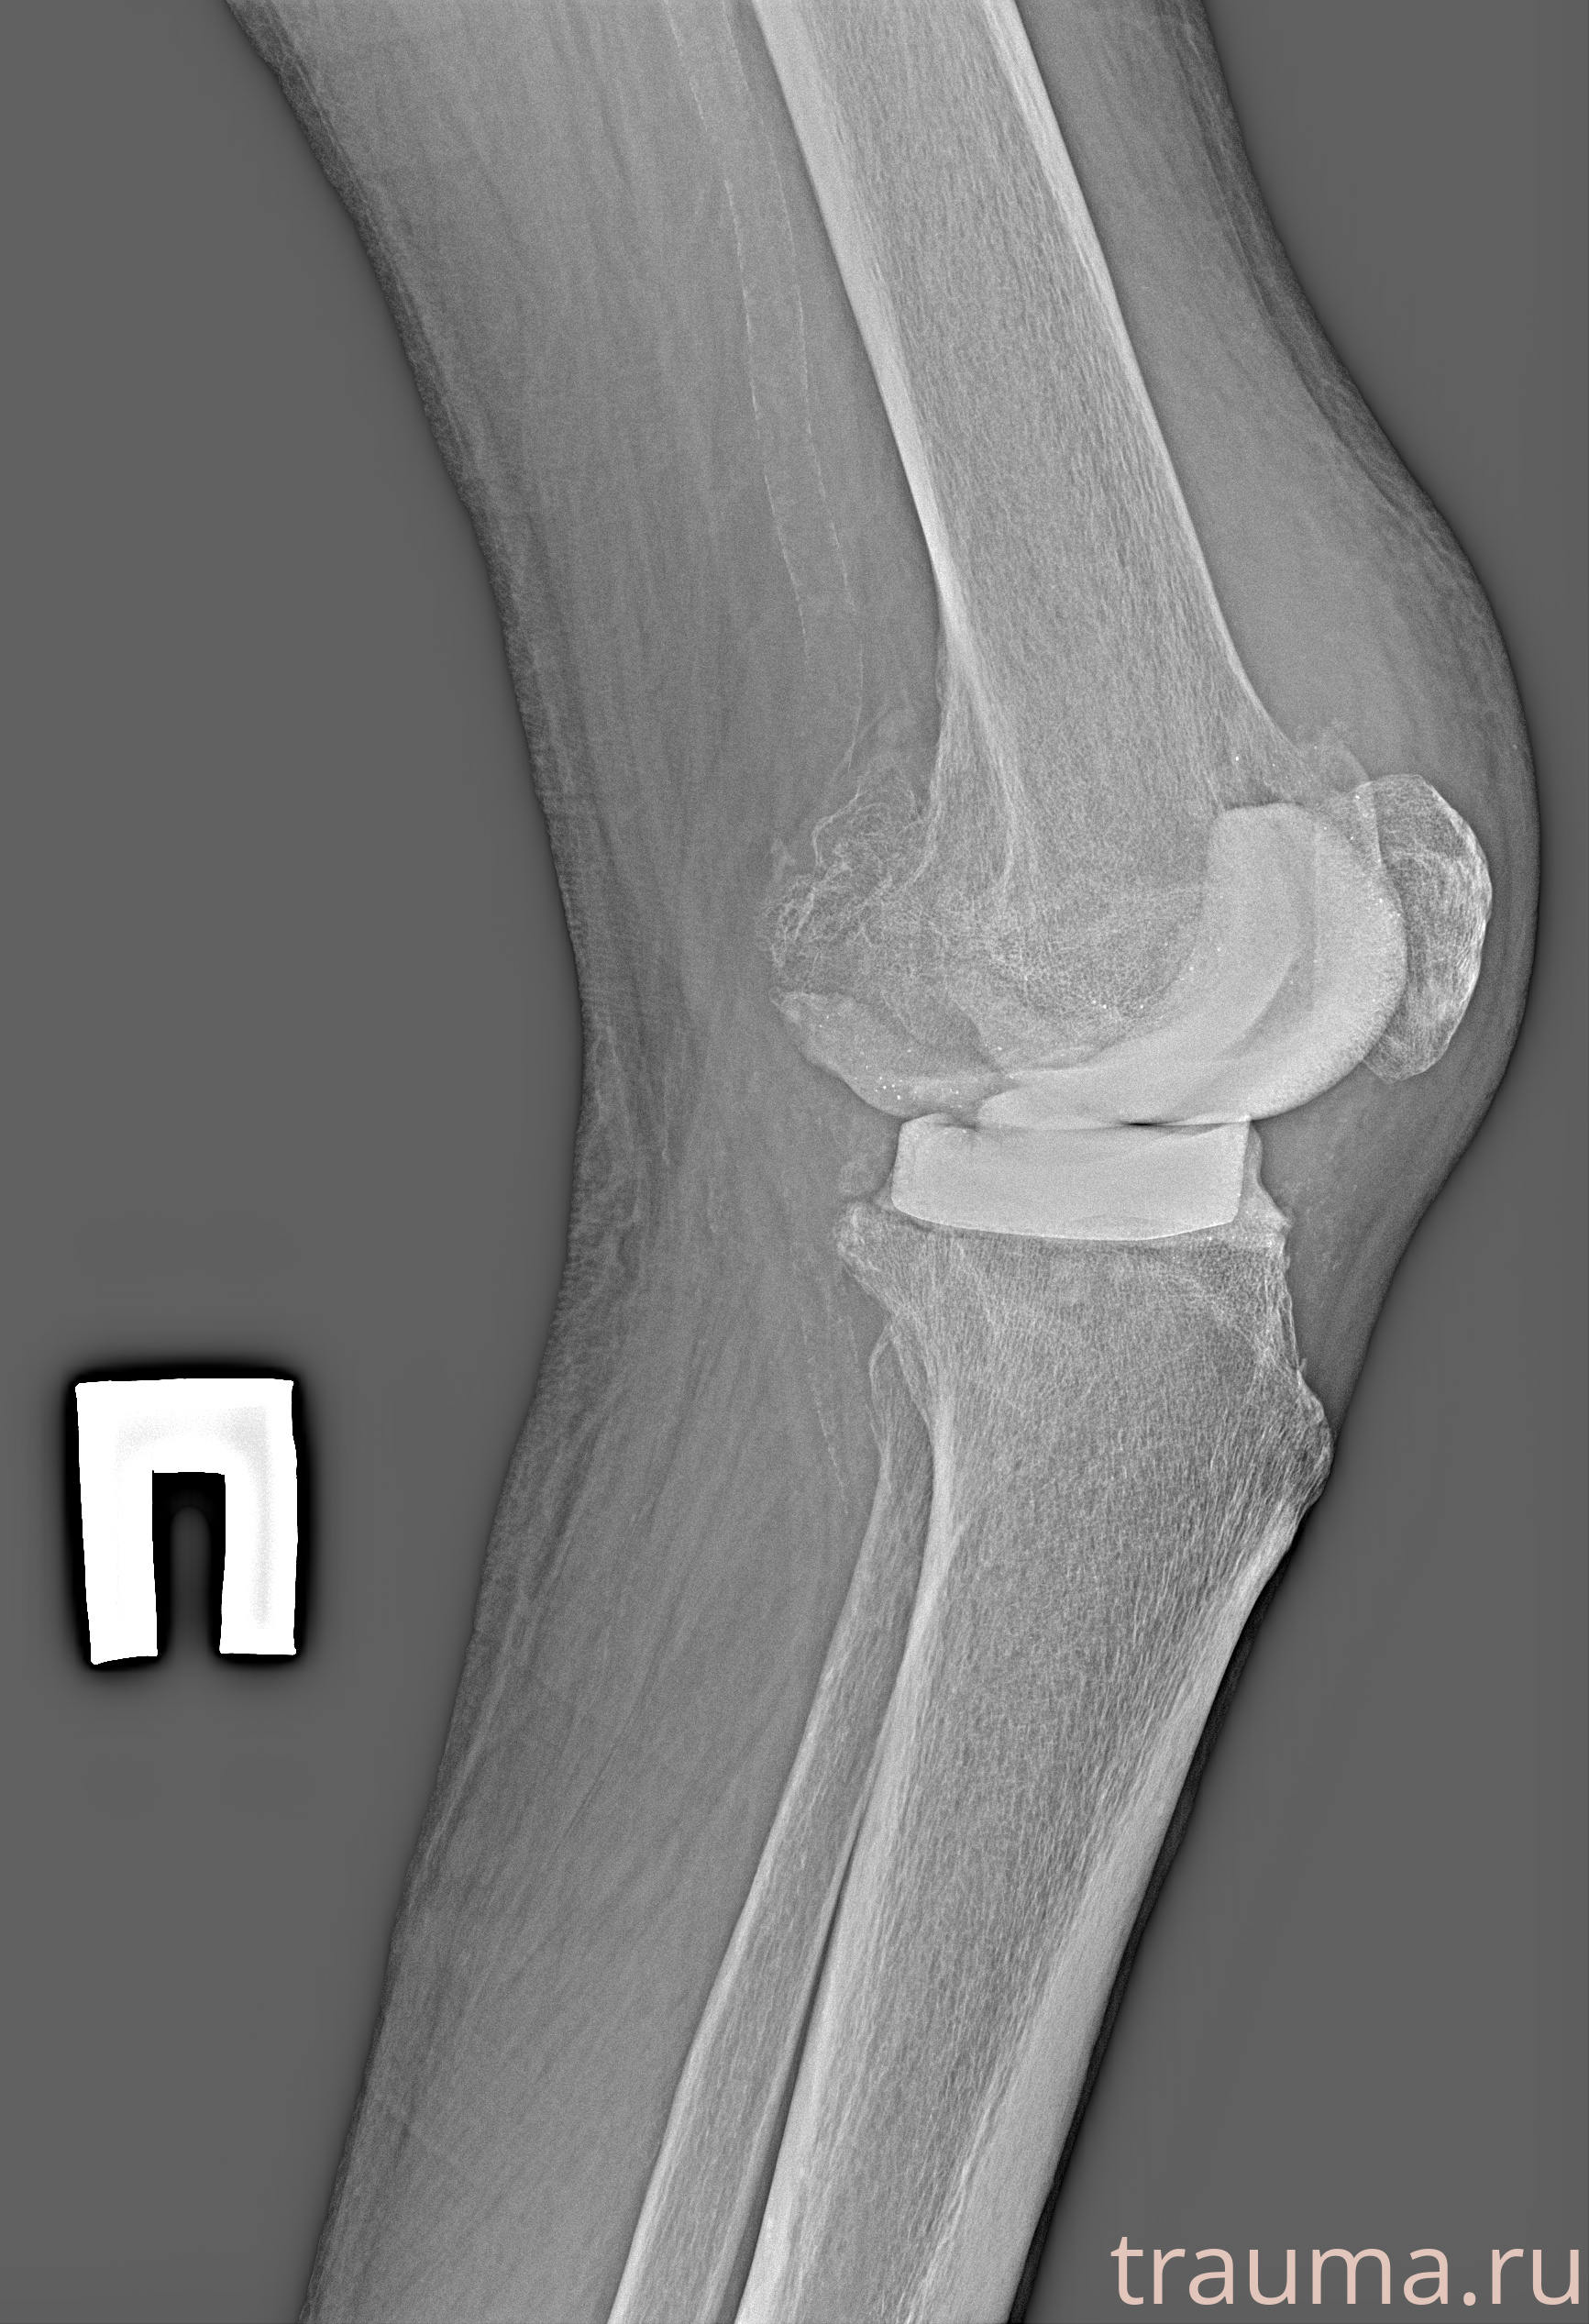

Рентген на дому: по вашему адресу приезжает врач-рентгенолог, травматолог-ортопед с мобильным рентгеновским аппаратом, проводит диагностику травмы или заболевания, делает необходимые рентгенограммы, дает рекомендации по дальнейшему лечению. Получить качественные снимки в домашних условиях возможно благодаря уникальной методике, разработанной МосРентген Центром для института  Склифосовского